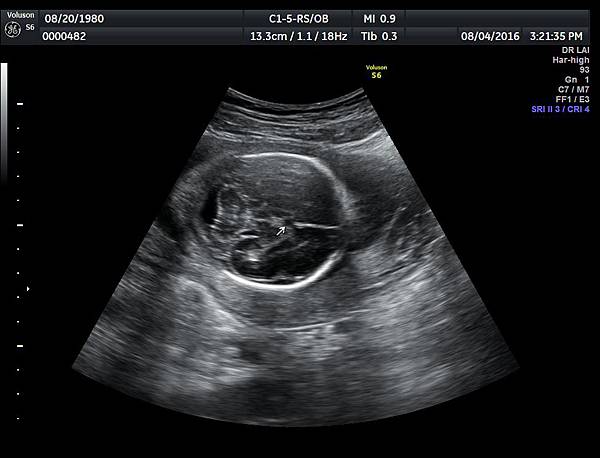

2016年8月4日在執行胎兒高層次超音波檢查時,我發現胎兒腦部的CSP(cavum septum pellucidum)很不清楚(附圖1~4),遇到這種情況,需要仔細評估胎兒腦部的駢胝體,因為CSP的天花板是駢胝體,CSP不明顯時,要合理的懷疑駢胝體沒有發育,或駢胝體下方有長東西(例如lipoma),駢胝體是連接左右大腦的神經纖維所組成。